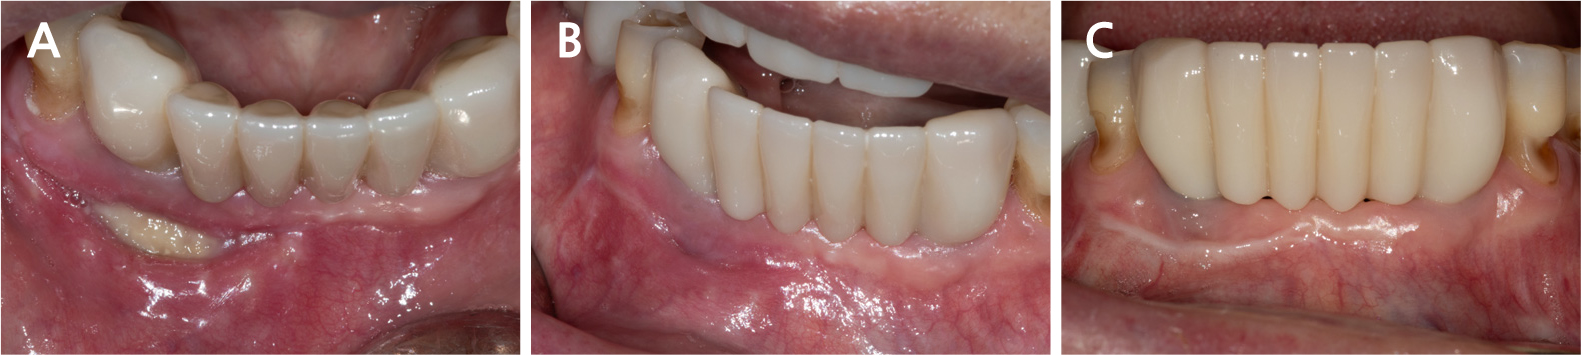

All surgical procedures were performed under local infiltration anesthesia using 2% lidocaine with 1:80,000 epinephrine. Fig. 3A shows the preoperative view. A horizontal incision with a vertical releasing incision at the distal end was made, including one or two adjacent tooth/implant crowns at the mucogingival junction (MGJ), using a #15c blade (Fig. 3B). Following mucoperiosteal flap elevation, the buccal fenestration (Fig. 3C) was apically expanded to approximately ∅5 mm circular window using a diamond drill from a sinus floor elevation kit (DASK Simple kit; Dentium, Suwon, Korea). Granulation tissue was detached and debrided using a surgical curette and hand instruments from the DASK Simple kit (Fig. 3D). The implant surface was decontaminated with a titanium brush (TN brush; Dentium) at 800 rpm under saline irrigation, followed by scrubbing with a cotton pellet soaked in tetracycline hydrochloride for 2 min (Fig. 3E and 3F). The peri-implant bone defect was filled with deproteinized porcine bone mineral (Osteon Xeno; Dentium) and covered with a porcine collagen membrane (Collagen Membrane II; Dentium) (Fig. 3G and 3H). Interrupted sutures were placed using a 6–0 monofilament nylon thread (Ethilon; Ethicon, Somerville, United States) to stabilize the wound (Fig. 3I). The patient was advised to avoid mechanical plaque control at the surgical site and to rinse twice daily with an antiseptic mouthwash (GUM dental rinse; Sunstar, Etoy, Switzerland) for 2 weeks. Antibiotics (clindamycin 150 mg, three tablets daily) and an analgesic (acetaminophen 600 mg, three tablets daily) were prescribed for 5 days to manage postoperative infection and pain. Symptoms resolved following surgery. The wound showed secondary healing at suture removal (2 weeks after surgery) and was fully closed by 4 weeks (Fig. 4). Radiographic bone fill was maintained at the 1.5-year follow-up (Fig. 5).